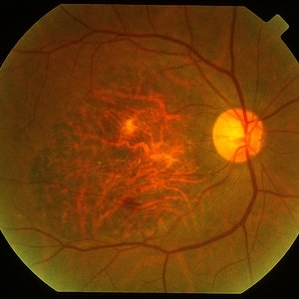

Age Related Macular Degeneration

Age Related Macular Degeneration

Mar 29 2013 by Henry J. Kaplan, MD

Geographic atrophy with small hemorrhages due to subretinal neovascular membrane development.

Condition/keywords: choroidal neovascularization (CNV), geographic atrophy